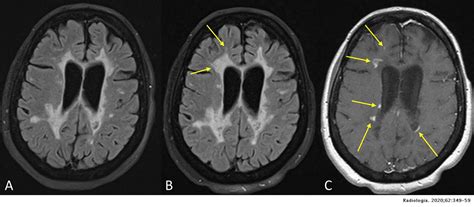

La disestesia es una sensación que se suele describir como dolor, picor, quemazón o de restricción. Proviene de dos palabras del griego antiguo que significan “sensación anormal”. Es el resultado del daño a los nervios y ocurre principalmente con afecciones neurológicas. Puede ocurrir debido a un derrame cerebral, síndrome del túnel carpiano y varios otros trastornos neurológicos. Según investigaciones, entre el 12 por ciento y el 28 por ciento de las personas con esclerosis múltiple (EM) sufren el ardor, hormigueo o dolor de la disestesia. La disestesia es un síntoma muy común de la esclerosis múltiple.

Imagen de resonancia magnética mostrando lesiones de esclerosis múltiple en el cerebro.

La esclerosis múltiple es una enfermedad autoinmune en la que el cuerpo daña o destruye la mielina, la capa de tejido graso protector que permite el paso de los impulsos eléctricos. Cuando el daño de la mielina es mínimo, solo puede afectar las señales de los nervios de manera leve o temporal. Sin embargo, un daño extenso de la mielina puede interrumpir por completo la comunicación entre los nervios, lo que generalmente causa un dolor intenso a largo plazo.